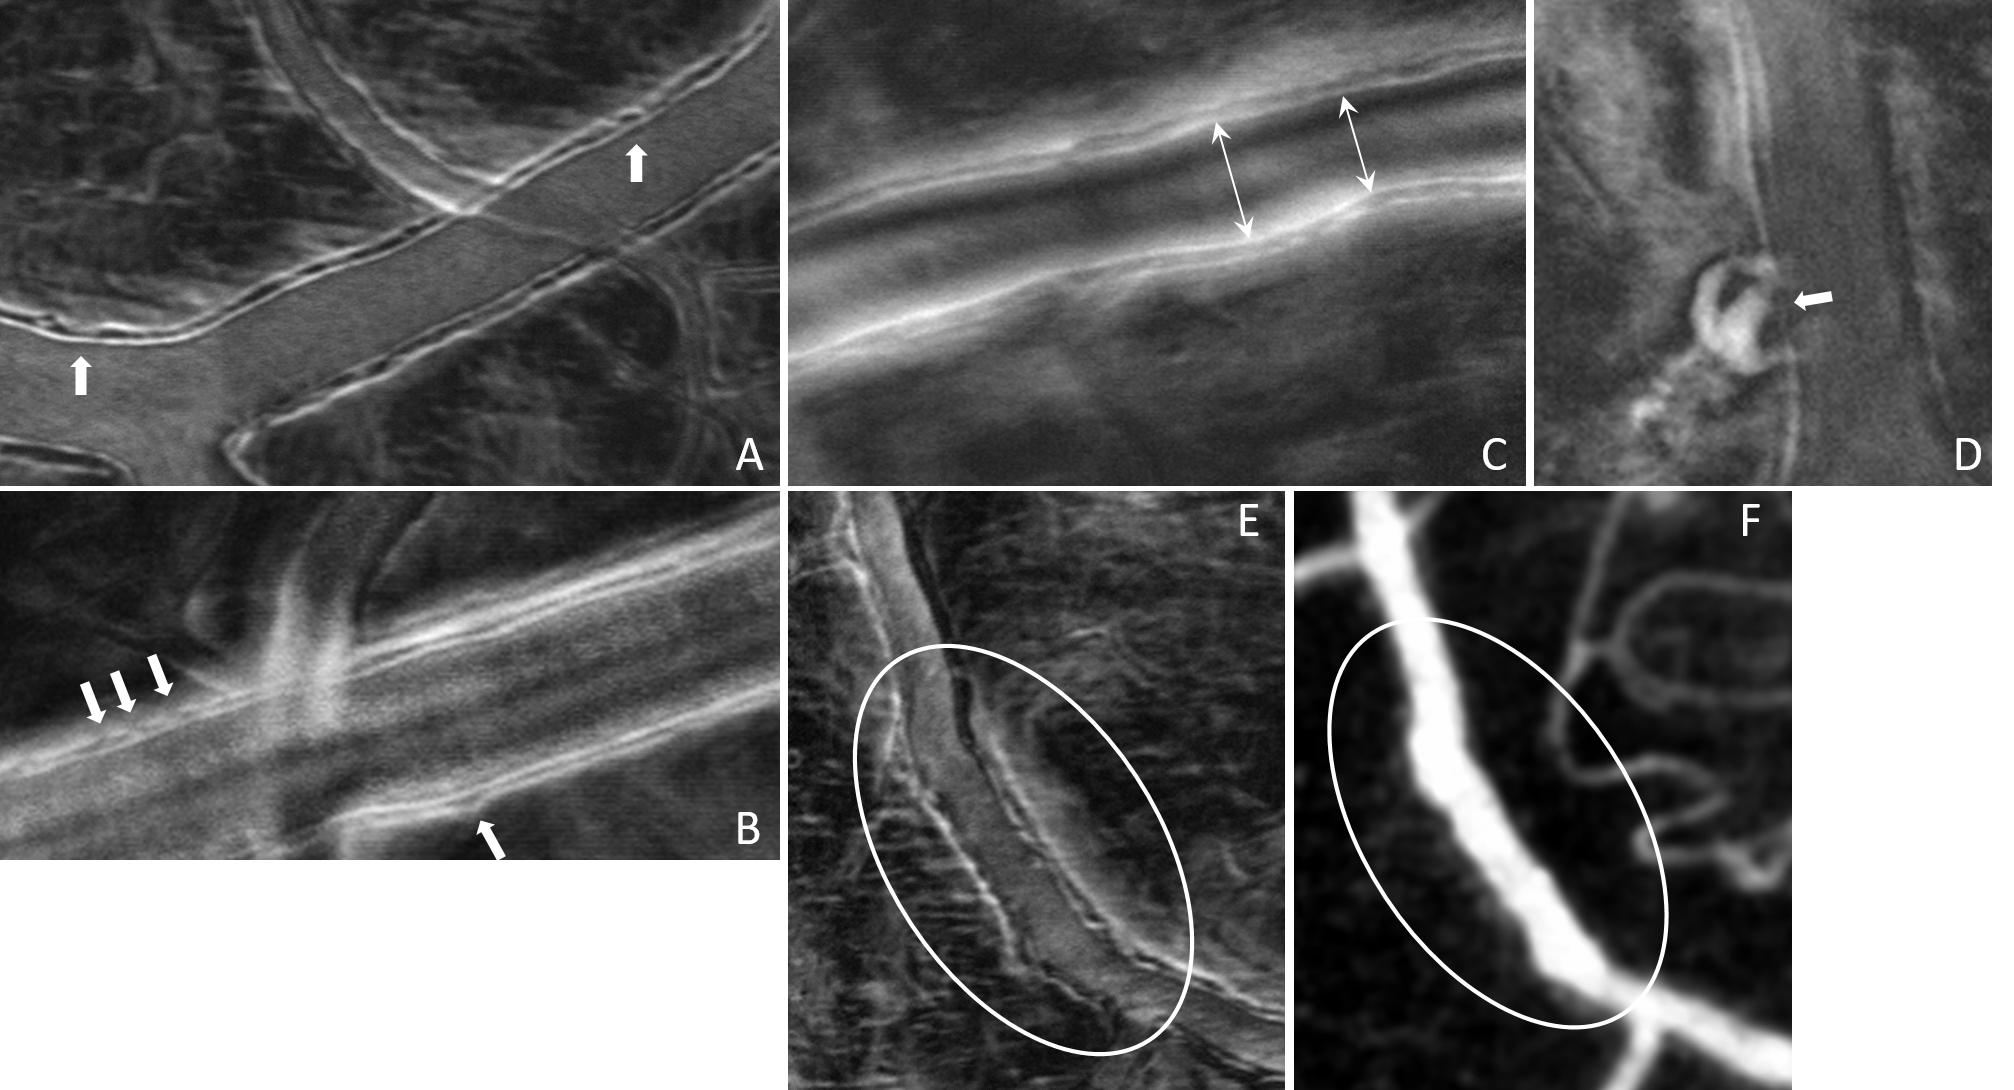

Phase gradient segmentation

“Cellular-Level Analysis of Retinal Blood Vessel Walls Based on Phase Gradient Images”, Diagnostics, 13(22), 3399, (2023)

Vessel wall disruptions visualized with phase gradient imaging